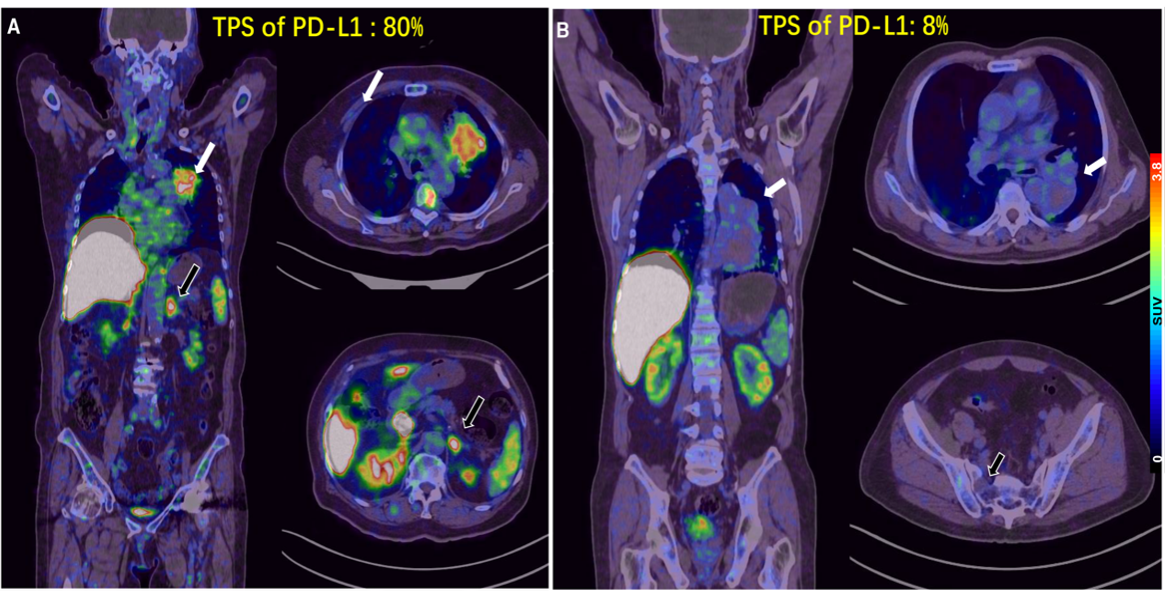

5.目前预测PD-1/PD-L1单抗疗效较为成熟的生物标志物主要是PD-L1表达。beat365唯一官方网站肿瘤医院核医学科和胸部肿瘤内一科合作,研制Ga-68标记的PD-L1靶向低分子量多肽(LMW)探针,首次用于进展期肺癌的临床转化研究展示了在可行的时间窗内用PET显像的方式对患者进行PD-L1表达水平检测的可行性和研究潜力。相关成果以First-in-human evaluation of a PD-L1-binding peptide radiotracer in non-small cell lung cancer patients with PET为题,于 2021年8 月发表在Journal of Nuclear Medicine杂志上。

图5: 68Ga-LMW在不同PD-L1表达水平肿瘤中的PET分析